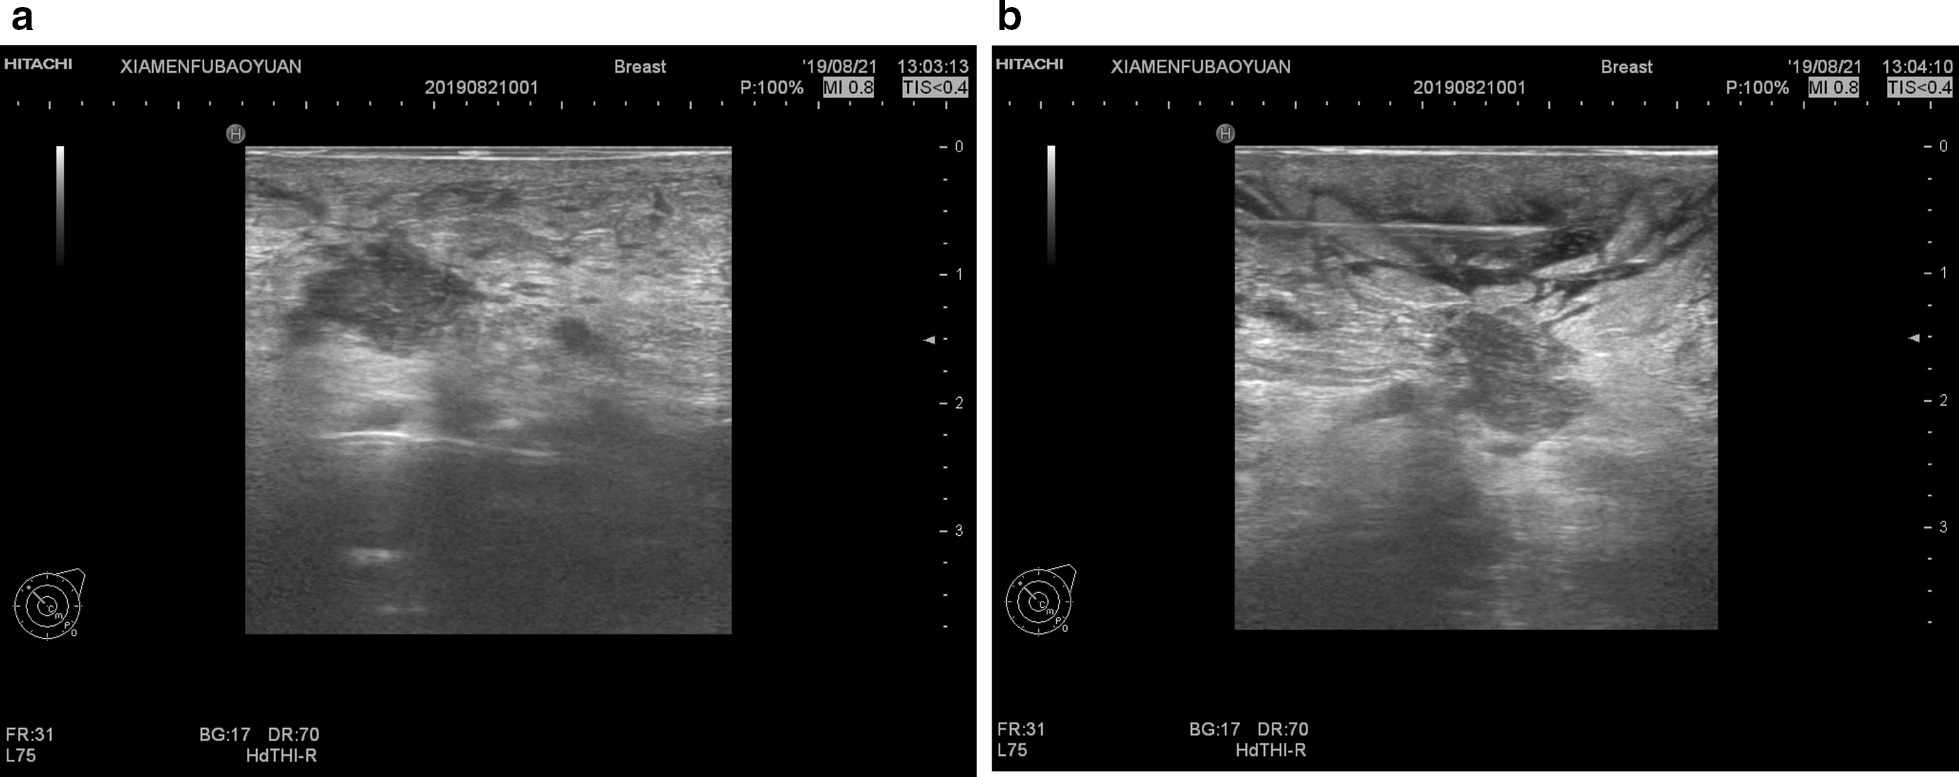

Mammotome Minimally Invasive Rotary Surgery System produced by Johnson & Johnson (sCM23; 8G sampling gun) and a digital color Doppler ultrasound diagnostic apparatus (MyLab™; 6–18.0 MHz in probe frequency) were used. Local anesthesia was given using a mixture of 20 ml of 2% lidocaine, 250 ml of 0.9% sodium chloride and 1 ml of epinephrine, with the final concentration of epinephrine being 4 μg/ml. We selected the submammary fold as the incision site, punctured the minimally invasive rotary cutter under the lesion and removed the lesion under the guidance of ultrasound. The scope of lesion resection consisted of palpable lesions, visible necrotic granulomatous tissues, inflammatory lesions including galactosis and dilated catheters and skin damages, and any suspicious hypoechoic nodules under intraoperative ultrasound, as well as dilated catheters and normal tissues within 0.5 cm of the surrounding area. After the withdrawal of the rotary cutter, diluted iodine and normal saline were administered through the needle tract until the flushing fluid was clear. After the operation, we placed a drainage tube through the needle tract to connect with a negative pressure ball for drainage. Appropriate compression bandage was applied for 48 h after operation. We observed the nature of the drainage tube every day. The tube was extubated when the drainage fluid was less than 5 ml for two consecutive days. The procedure of minimally invasive resection is shown in Figs. 3 and 4.

Fig. 3.

Ultrasound-guided minimally invasive rotary surgery procedure. a Under ultrasound guidance, the probe was punctured under the lesion with the groove facing the lesion; b During the resection, the ultrasound probe was kept parallel to the probe cutting groove. Under the ultrasound guidance, the angle of the cutting groove was switched in a fan shape, and the probe, target lesion and the cutting groove was kept in the same plane; c After the resection, the cutting groove was closed and the probe was withdrawn; d No obvious border between the lesion and the normal tissues was observed in the resected gross biopsy, and the dilated catheter was filled with erosive and necrotic tissues

Fig. 4.

Local infiltration of anesthesia guided by ultrasound. a Anesthesia in the posterior breast space; b Anesthesia in the subcutaneous tissue space